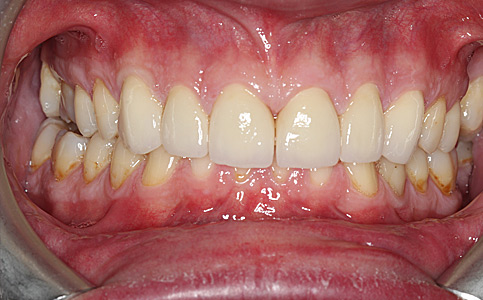

Dzięki koronom pełnoceramicznym w szczęce i żuchwie oraz uzupełnieniu braków zębowych implantami, pacjentka może znów się szeroko i pięknie uśmiechać.

Zobacz efekty przeciągając suwak w prawo lub w lewo.